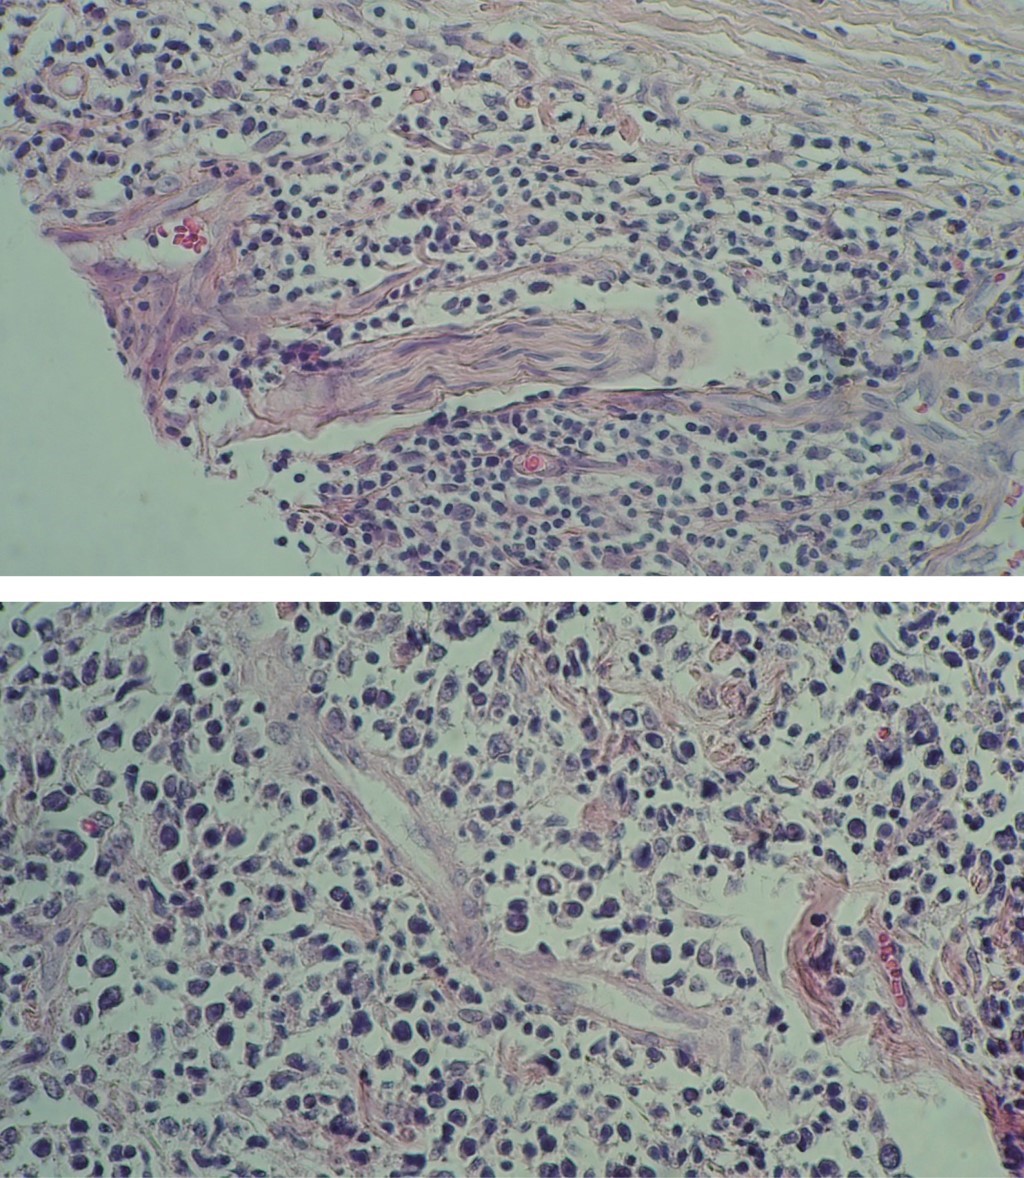

Se realiza biopsia incisional, con reporte histopatológico de epidermis con acantosis regular, en dermis superficial se aprecia una banda normal de colágena (Figura 3) por debajo de la cual se observa un denso infiltrado que ocupa el resto de la dermis, está constituido por linfocitos atípicos, con núcleos pleomórficos grandes, hipercromáticos y con mitosis anormales (Figuras 4, 5 y 6).

Inmunohistoquímica: CD-20 y MUM-1: positivo; CD-10, BCL6, CD-3, CD-30: negativos. El diagnóstico histopatológico fue linfoma B difuso de células grandes no centro germinal.

Éste se realiza al llevar a cabo una biopsia, cuyo estudio histopatológico muestra infiltrado denso y difuso en la dermis, constituida por células grandes que son los inmunoblastos y centroblastos, este infiltrado puede extenderse hasta el tejido celular subcutáneo. La inmunohistoquímica es positiva para CD20, CD79, Pax-5, Bcl-2, MUM1/IRF4 y FOX-P1, negativa para CD10 y Bcl-6.9